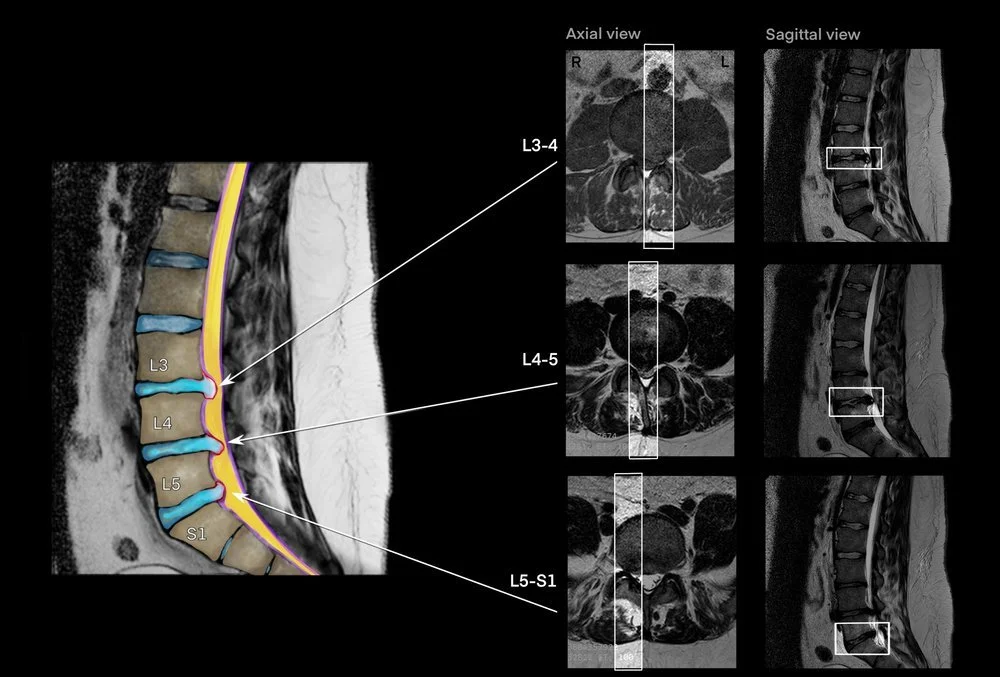

Sagittal view L3-4, L4-5, and L5-S1 herniation composite call-outs

Pre-surgical MRI composite colorization visual summary